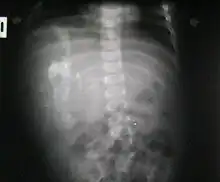

Fetus in fetu (or foetus in foetu) is a rare developmental abnormality in which a mass of tissue resembling a fetus forms inside the body of its twin. An early example of the phenomenon was described in 1808 by George William Young.[1]

Fetus in fetu may be a parasitic twin fetus growing within its host twin. Very early in a monozygotic twin pregnancy, in which both fetuses share a common placenta, one fetus wraps around and envelops the other. The enveloped twin becomes a parasite, in that its survival depends on the survival of the host twin, by drawing on the host twin's blood supply. The parasitic twin is anencephalic (without a brain) and lacks some internal organs, and as such is unable to survive on its own. As the host twin has to "feed" the enveloped twin from the nutrients received over a single umbilical cord, they usually die before birth.